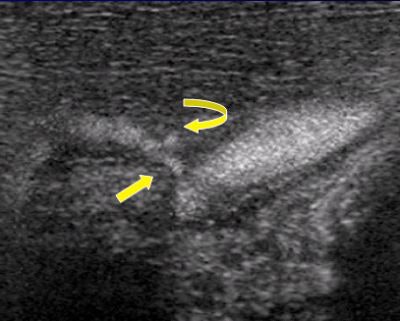

![]() |

| B-flow image provides improved definition of the vessel lumen (straight arrow) and demonstrates ulceration, which was not detected on the Doppler study but confirmed at arteriography. Images courtesy of Dr. John Pellerito. |

B-flow benefits include improved carotid plaque characterization and better demonstration of arterial stenosis and turbulent flow states. B-flow also offers potential in evaluation of high-flow lesions in dialysis fistula and bypass grafts, where color-flow artifacts can obscure the underlying stenosis.